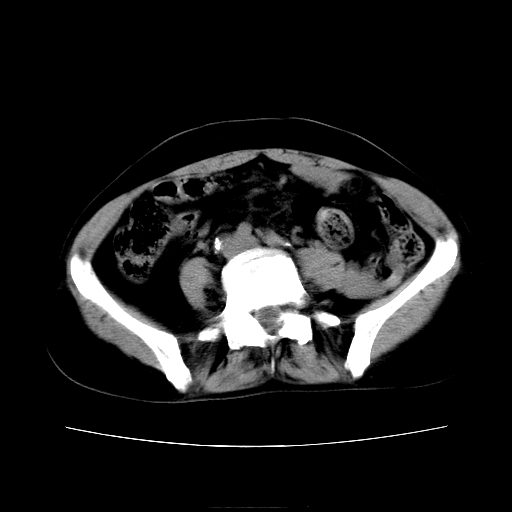

女45y多次(7次)碎石,结果不理想!曾碎石后尿出小碎石,仍腰痛,要求ct,其它不详.本人更倾向于钙化斑!无肾实质破坏,积水等提示集合系统无梗阻.另外腹腔多处钙化.是否结核后改变!谢谢赐教!

1)双肾结石。2)脾脏钙化灶。3)腹膜后多发淋巴结钙化。

尿路结石与腹部淋巴结钙化共存,建议v尿路造影检查,免得钙化灶冤枉为结石受罚。

考虑双肾结石,肾脏实质无破坏表现,没有结核病史,不考虑肾结核,